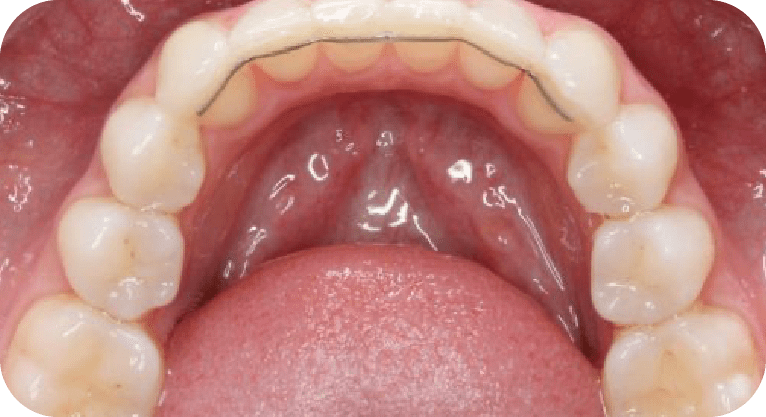

Paciente masculino, “25” años

Tratamiento: Tratamiento de conducto

El paciente presentaba dolor en dos molares por caries profundas. Se realizó endodoncia en ambas piezas, desinfectando y sellando los conductos, seguido de coronas de zirconio para restaurar su función.